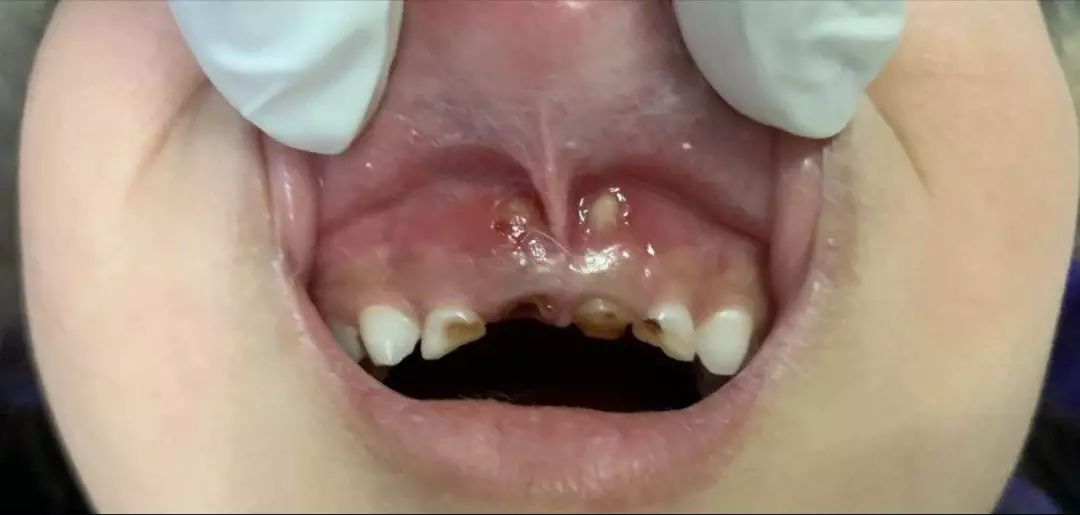

乳牙根尖周炎破壞牙槽骨并穿破粘膜

乳牙根穿破粘膜并形成創(chuàng)傷性潰瘍

而且有這樣的一種現(xiàn)實(shí),哪怕全口牙齲壞也鮮有家長為此主動(dòng)去看牙醫(yī),更多的是當(dāng)孩子出現(xiàn)了劇烈牙痛或者牙齦上長出了令家長們驚恐的如圖示腫物(恐癌心理)才被迫就診,這是一種中國式特色——反正乳牙都是要換掉的,單純齲齒治不治無所謂。

1、嚴(yán)重的也是常見的危害,并不是齲齒本身,而是齲齒進(jìn)展帶來的并發(fā)癥,它可進(jìn)一步發(fā)展為牙髓炎(劇烈牙痛)、根尖周膿腫,瘺管,甚至擴(kuò)散至頜周間隙感染,嚴(yán)重者會(huì)形成頜面部蜂窩織炎甚至引起敗血癥,可危及生命。中國大部分三甲醫(yī)院口腔科,每年都免不了收治些重癥牙源性間隙感染的患兒住院,無一不是來源于一顆小齲齒的慢性進(jìn)展。

2、對(duì)恒牙及恒牙列的影響。乳牙的齲齒引起慢性根尖炎癥長期刺激其根周的恒牙胚,導(dǎo)致恒牙萌出后即出現(xiàn)釉質(zhì)發(fā)育不全,稱為“特納牙”。另外,乳牙因齲早失后可致恒牙換牙時(shí)失去咬合誘導(dǎo)而長得亂七八糟,得依靠后期牙齒矯形來糾正,費(fèi)時(shí)費(fèi)力費(fèi)神費(fèi)錢。